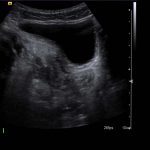

- Superficial to this is a 2 x 2.5 cm ovoid hypoechoic structure which appears separate from the adjacent bowel and shows no internal vascularity

Superficial to this is a 2 x 2.5 cm ovoid hypoechoic structure which appears separate from the adjacent bowel and shows no internal vascularity, concerning for a periappendiceal abscess.